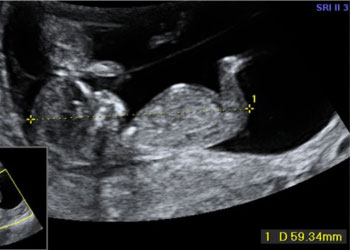

Ejemplos de ecografías del embarazo